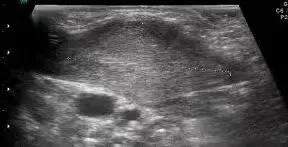

肿块型胸锁乳突肌彩超表现是这样的